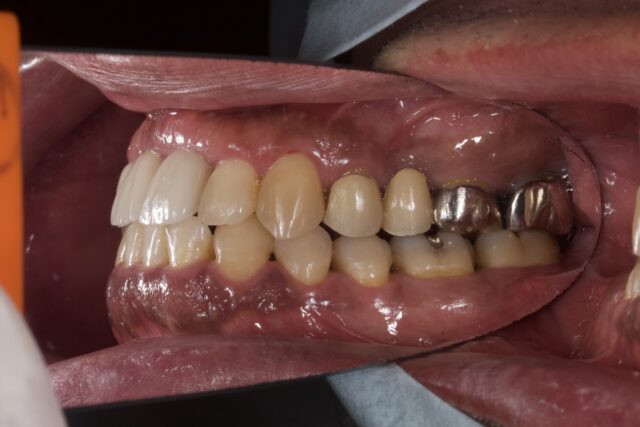

before

after